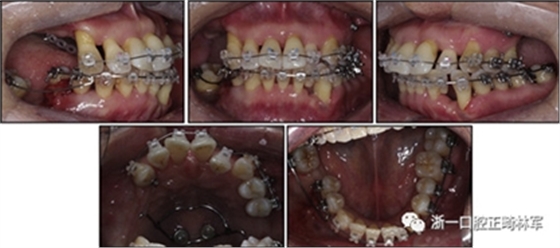

一名因多顆牙齒缺失和牙周損傷的49歲婦女被牙周科送往國民健康保險服務(wù)一山醫(yī)院的正畸科進行跨學(xué)科綜合治療。多顆后牙已在10天前被拔除。她的主訴是前牙列擁擠,她想改善美觀和功能。她的病史沒有提供有用信息,她沒有顳下頜關(guān)節(jié)紊亂的跡象??谕鈾z查顯示面部對稱,休息位時嘴唇不適,尖銳鼻唇溝和突出的嘴唇。她的下頜牙齒中線偏移到面部中線的左側(cè)(圖1)。

圖1. 治療前面部和口內(nèi)照片

口腔內(nèi)由于牙周炎,她的上頜右側(cè)第一和第二前磨牙,上頜右側(cè)第一和第二磨牙,上頜左側(cè)第一和第二磨牙以及下頜右側(cè)第一磨牙缺失。牙周探查顯示在磨牙區(qū)域和下頜骨左側(cè)側(cè)切牙區(qū)有深的牙周袋,還存在出血(表I)。上頜骨和下頜骨前牙擁擠,左側(cè)側(cè)切牙存在反合,下頜左側(cè)側(cè)切牙發(fā)過度萌出。覆蓋是5毫米,上頜切牙是唇傾的。在上頜弓中,尖牙和前磨牙是近中傾斜,右側(cè)尖牙過度萌出。而且,下頜右側(cè)第二磨牙向近中傾斜。尖牙處于I類關(guān)系,但無法評估磨牙關(guān)系(圖1和2)。